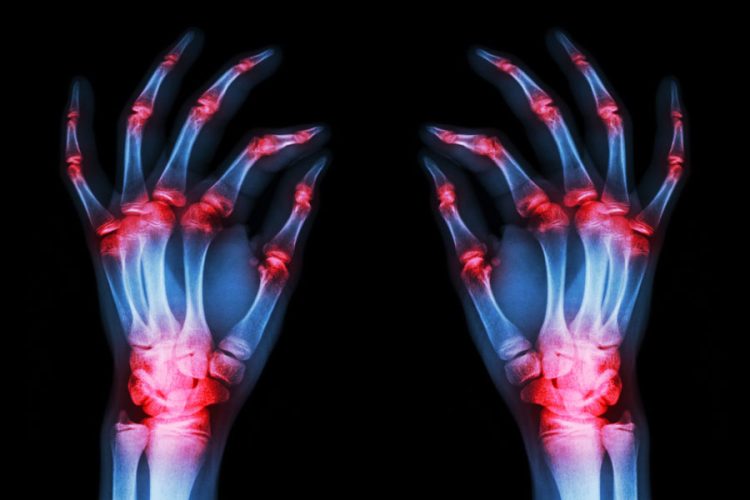

Caracterizada por cambios inflamatorios en la membrana sinovial de las articulaciones y artritis erosiva, la artritis reumatoide ha ganado más recientemente una atención cada vez mayor debido al estrés oxidativo, que se cree que es un factor clave en el desarrollo de la afección. Tanto las mitocondrias como la sangre de los pacientes con AR han exhibido niveles elevados de especies reactivas de oxígeno, que es un biomarcador prominente del estrés oxidativo. Posteriormente, estas especies pueden causar daños en el cartílago articular ya sea directa o indirectamente, lo que lleva a la degradación de los proteoglicanos y a la inhibición de su síntesis. La patogénesis de la catarata también está relacionada con el estrés oxidativo, con un desequilibrio en el estado redox del cristalino impulsado por este estrés y que contribuye al desarrollo. Además, el estrés oxidativo acelera la pérdida de células epiteliales del cristalino, que también es un factor crítico en el desarrollo de cataratas.

Pasando a otros aspectos de la enfermedad, la AR también implica la inflamación local como elemento central en su desarrollo. Los factores inflamatorios y las quimiocinas del factor de necrosis tumoral, las interleucinas y la metaloproteinasa de la matriz están regulados al alza en los macrófagos sinoviales y en los subconjuntos de células dendríticas en pacientes con AR. Con esta regulación al alza, los mediadores inflamatorios conducen a la degradación del cartílago, la erosión ósea y el desarrollo acelerado de la AR. La inflamación también juega un papel fundamental en la patogénesis del glaucoma. Los mismos factores inflamatorios del factor de necrosis tumoral, dos interleucinas diferentes y la metaloproteinasa de la matriz pueden promover la muerte de las células ganglionares de la retina, un sello distintivo del desarrollo del glaucoma.